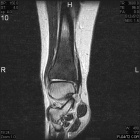

15 year old female complains of ankle pain for three months

Zoom image: Radiological image Radiological image.